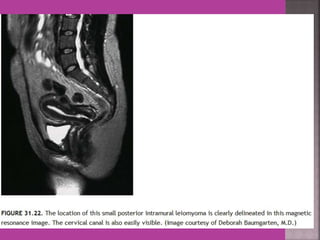

 Myoma—to differentiate myoma from

adenomyoma.localization of myoma—sub

serous/ intra mural or sub mucous.